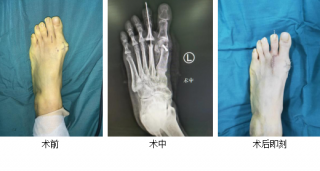

第三代微创踇外翻矫正手术

sararz足踝团队采用4毫米低频超声骨刀微创截骨,切口很小无需缝合;低频超声骨刀锋利、精准、自带注水降温,能更好地保护骨骼血运,使得截骨处更快愈合,手术基本无血渗出,完美修整踇外翻,术后第二天就能下地行走。

74岁奶奶踇外翻畸形10年,1cm小切口微创矫形助老人轻松行走

上周,betway在线登陆足踝科石荣剑副院长徐明亮主任团队采用第三代微创踇外翻矫形技术,为一位双足踇外翻畸形10年的74岁